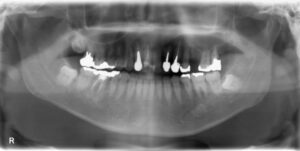

前歯3本欠損症例

前歯3本欠損症例 BEFORE AFTER 46歳女性/上3本欠損/インプラント埋込手術 【治療内容】 前歯3本に根尖病…